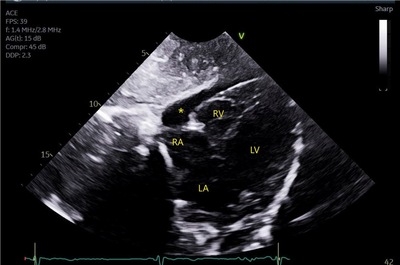

A 21-year-old female with depression presented with two days of sharp, positional chest pain, dyspnea, palpitations, and weakness. She reported eating less than one meal per day, running 22 miles daily, self-induced vomiting, and experiencing one year of amenorrhea. On exam, her BMI was 10.7 kg/m^2, with lanugo, proximal muscle weakness, and a pericardial friction rub. Labs showed hypokalemia, hypophosphatemia, transaminitis, elevated CK, and leukocytosis. ECG demonstrated diffuse ST elevations and PR depression in aVR. Transthoracic echocardiography revealed a moderate pericardial effusion without tamponade (Figure 1). CT chest showed pneumomediastinum and subcutaneous emphysema without evidence of esophageal perforation (Figure 2). Workup for infectious, autoimmune, ischemic, and thyroid causes was negative. She was diagnosed with severe AN and major depressive disorder. Management included IV fluids, electrolyte repletion, and nutritional support. Pericarditis was treated with ibuprofen and colchicine. Psychiatric therapy included olanzapine and mirtazapine for appetite stimulation and mood support. She was discharged to a structured inpatient nutritional rehabilitation program.

This is the first reported case of symptomatic pericarditis in AN. While pericardial effusions are often asymptomatic and linked to myocardial and pericardial fat loss, this case suggests purging-induced esophageal microperforations may cause subclinical mediastinitis, triggering pericardial inflammation. Cardiovascular complications occur in up to 87% of patients with AN. A high index of suspicion for pericarditis is warranted in malnourished patients presenting with chest pain. ECG, echocardiography, and imaging are essential.